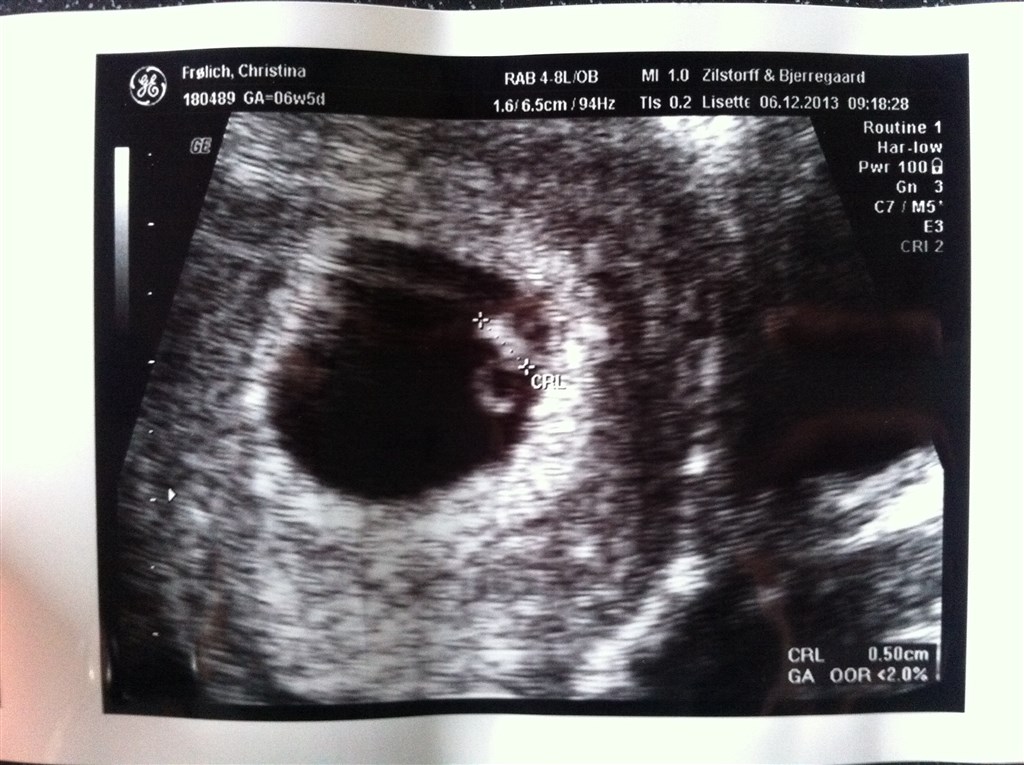

Vi har idag været til tidlig scanning af denne lille, og det må man sige, 5 mm lang.. men alt så ud som det skal, fine og regelmæssige hjerteslag og blommesæk.. Jordmoderen målte babyen til 6+2 men min livmor til 6+4 , så lige nu er termin mellem den 28-30. juli.. Var så skønt at se alt var som dette skulle være..